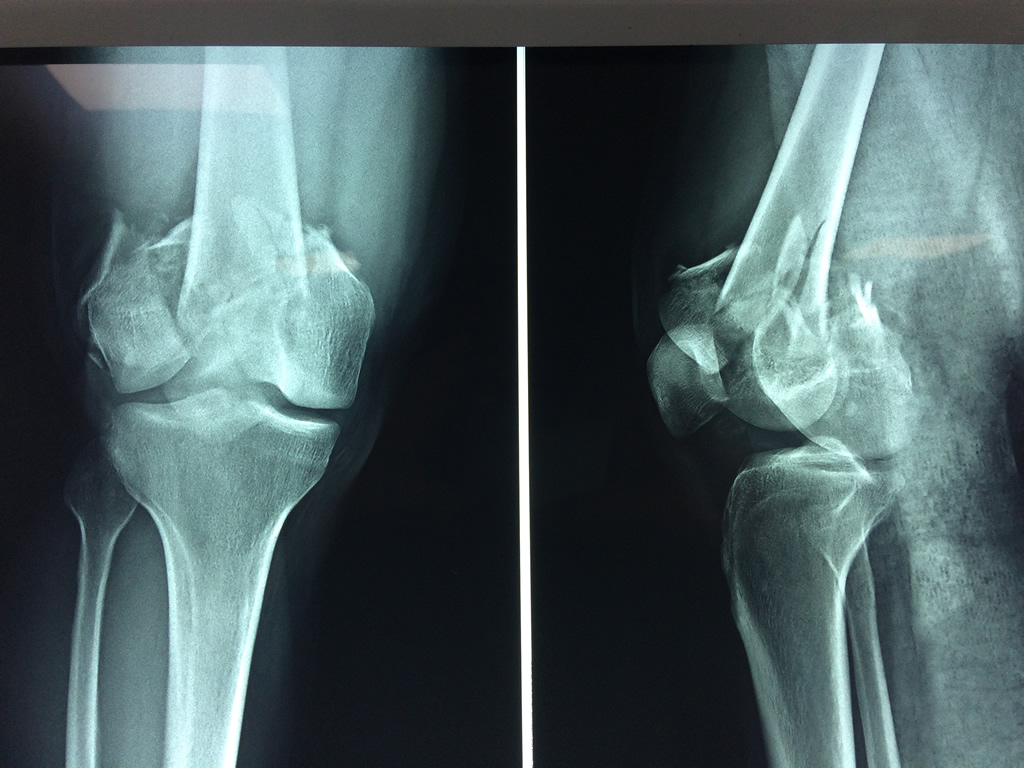

Cirugias en El Salvador - Fémur

El fémur es el hueso del muslo, el segundo segmento del miembro inferior. Es el hueso más largo, fuerte y voluminoso del cuerpo humano.